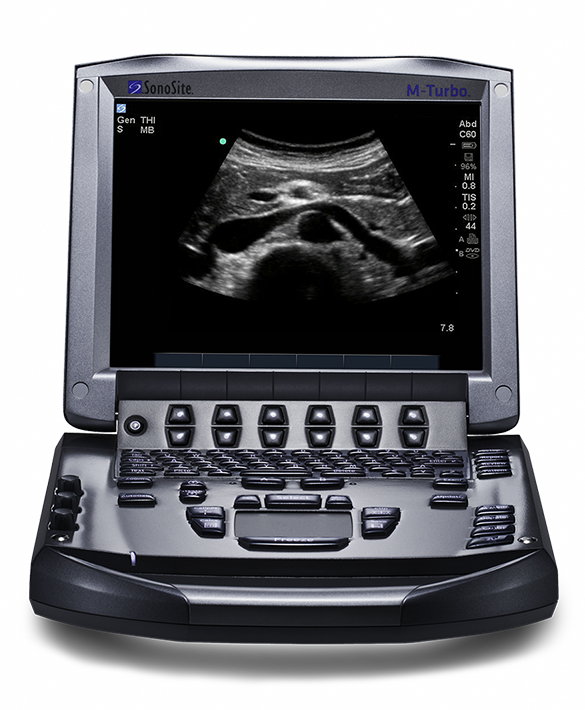

The potential impact of a new point-of-care ultrasound system in the Mosul hospital could be far-reaching, and so Dr Pich approached FUJIFILM Sonosite for support for his return mission and a Sonosite M-Turbo system was donated. Dr Pich explained:

“I know this machine well and was very happy to take it to Mosul. It is small, light and easy to carry in one hand. It has excellent probes of various types that are resilient and reliable, and the whole system is intuitive to use and easy to teach to others. In a critical care setting, time is of the essence and this ultrasound machine boots up within a few seconds and is ready for use straightaway.”

“There is some life on the streets again, security has greatly improved and, although there is still a lack of basic materials in the hospital, staff continue to work there with enthusiasm and dedication. It was a pleasure to hand over the M-Turbo and deliver the training course to surgeons and radiologists. I talked about regional anaesthesia, guiding needle insertion, and how to interpret views of structures and identify nerves; I had a practice pad and needles with me, so they could each experience a simulated exercise. Then one radiologist on the course was very keen to use it to guide her in taking biopsies of breast tissue, which was an application of the device that I hadn’t foreseen. As soon as the course was over, the Iraqi attendees took the M-Turbo to the emergency room to assess a woman with a hernia in the abdominal wall – it was very satisfying to see it being used immediately and effectively to raise the level of care they could provide.”

The Sonosite M-Turbo ultrasound system gives you striking image quality with sharp contrast resolution and clear tissue delineation.